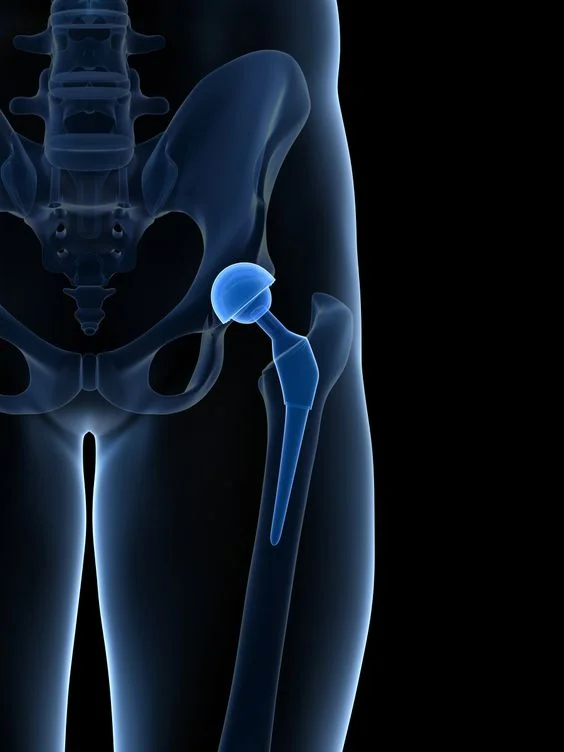

Total joint replacement patient Guide